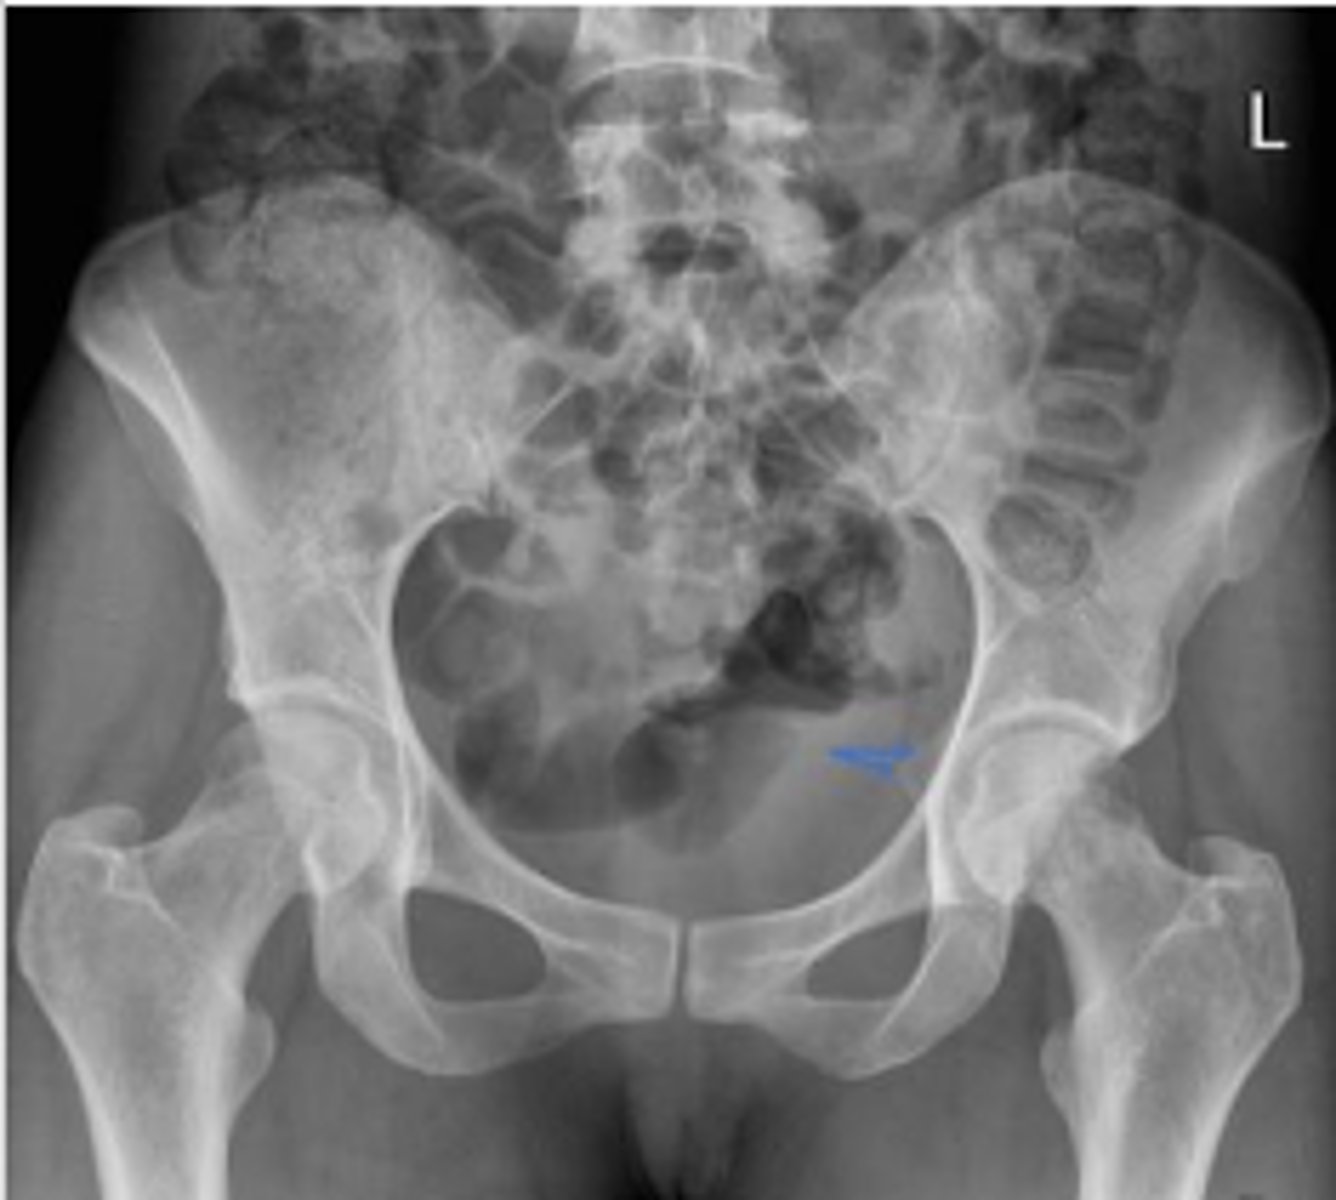

AP pelvis or bilateral hips

What is the name of the radiographic view?

Phleboliths

What are the arrows pointing to?

Pubic symphysis

What joint space is the arrow pointing to?